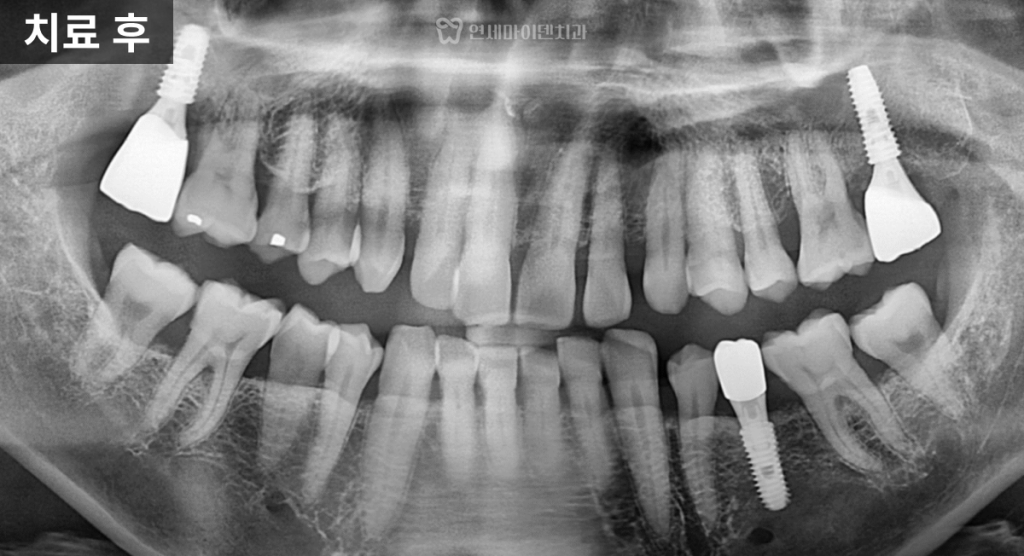

4년 경과: 결과는?

이번 케이스는

4년이 지난 현재까지✔ 임플란트 안정적 유지

✔ 주변 치아 뼈 레벨 유지

✔ 정기 관리 지속임플란트의 수명은